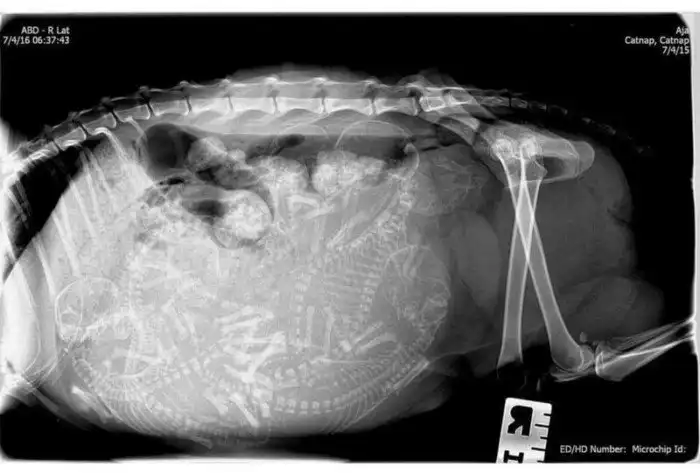

3. Беременная кошка